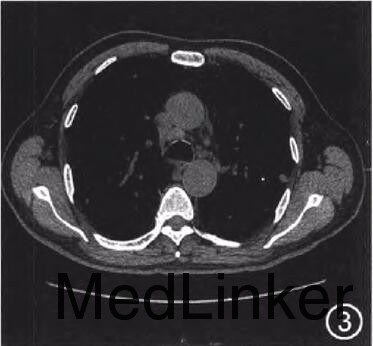

查体:未查见特殊 辅查:单核细胞百分比0.15(参考值0.03~0.13),c反应蛋白13.9mg/L(参考值<7.9mg/L),甲胎蛋白、癌胚抗原、CAl25、CAl99、CA153阴性,真菌-D-葡聚糖:97ng/L(参考值<80ng/L),曲霉菌半乳甘露聚糖0.19(参考值<0.50),自身抗体谱:抗内皮细胞抗体(+),抗核抗体、抗ENA抗体、抗线粒体抗体阴性。胸片示(图1):双肺野弥漫多发团片状、结节状高密度影,边界不清,双下肺为著。胸部CT提示(图2,3):双肺野弥漫多发团片状、结节状及索条状高密度影,大部分边界不清,以双下肺为著,部分结节内可见小空泡;纵隔多发大小不等淋巴结影,较大者约2.3cm×l.3cm。行肺内结节穿刺活检,病理检查:镜下见肺组织纤维化,淋巴、浆细胞浸润,可见多核巨细胞及坏死,符合肉芽肿性炎症性病变(图4)。免疫组织化学染色结果:PAS染色(-),抗酸染色(-)。活检组织块真菌培养阳性,六胺银染色检见孢子,病理见大量化生的纤毛柱状上皮细胞、大量炎细胞及坏死碎屑,未见恶性肿瘤细胞。